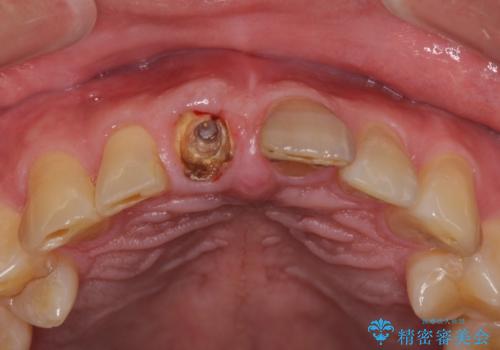

- 前歯の被せものが脱離したとのことで来院された患者様です。

診察の結果、前歯が縦に破折しており、抜歯が必要と診断されました。

補綴治療としては、インプラントあるいはブリッジの2つがありますが、患者様と相談した結果、インプラントによる補綴治療を選択することとなりました。